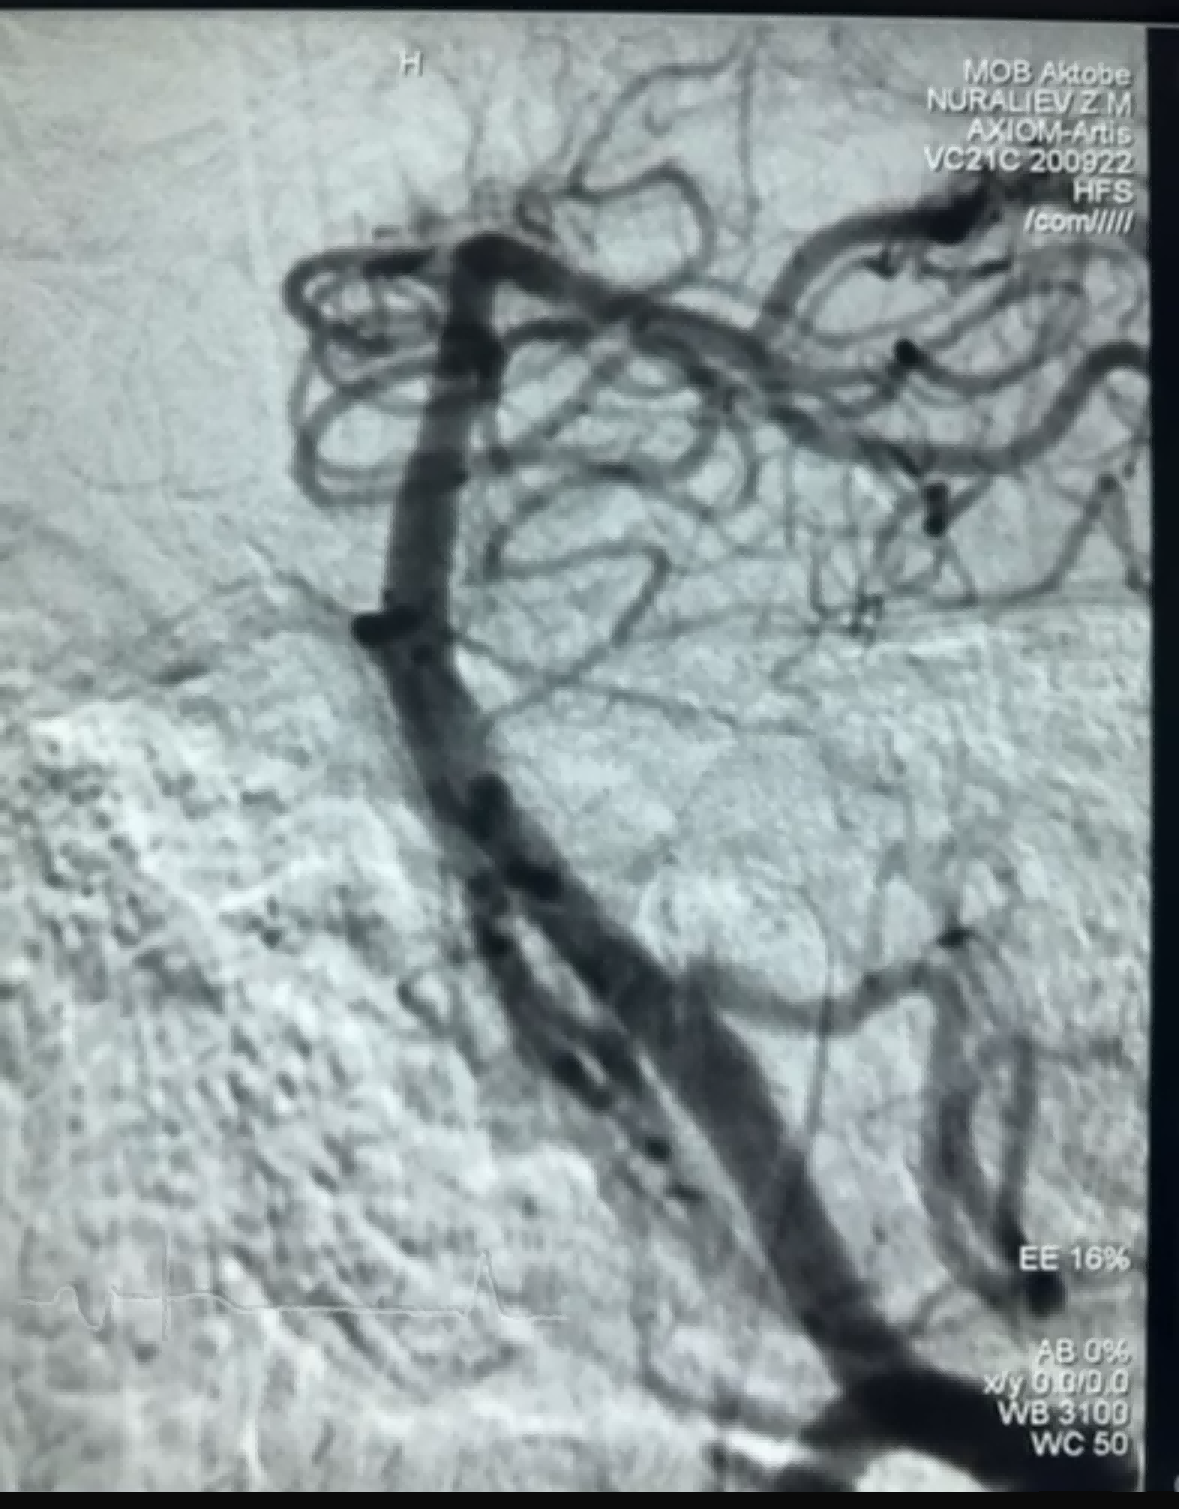

Baru-baru ini, terdapat kes trombektomi yang berjaya menggunakan Dredger Stent Retriever dari NeuroSafe Medical Co., Ltd. Dredger Stent Retriever mempunyai hujung lembut yang tidak invasif, yang dapat mengurangkan risiko kerosakan intim dengan banyak, dan mempunyai lubang berbentuk khas yang unik reka bentuk yang menangkap bekuan darah terutamanya dengan mengapit perubahan jurang.